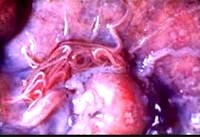

Trên người, các ấu trùng giai đoạn 3 bị nuốt vào không trưởng thành nhưng lại tấn công và di chuyển. Bản chất của nhiễm trùng này là phá hủy xảy ra khi thông qua cơ chế tổn thương cơ học hoặc qua trung gian độc tố, cũng như các phản ứng viêm tại chỗ trên vật chủ do ấu trùng Gnathostoma. Nhiễm trùng loài Gnathostoma điển hình thường được phân loại thành thể da niêm mạc, thể phủ tạng và thể thần kinh trung ương. Nhiễm trùng Gnathostoma có thể gây ra các triệu chứng mà có tái phát trong vòng 10-12 năm, ngược lại nhiễm trùng Angiostrongylus có thể gây các triệu chứng tái phát trong vài tháng. Triệu chứng tái hồi từng đợt có thể dẫn đến thách thức trong chẩn đoán bệnh.

Các đặc điểm trên da của nhiễm ấu trùng Gnathostoma gồm có viêm mô tế bào, hội chứng ban trườn và giả viêm nang lông bất cứ vị trí nào trên thân mình. Các tổn thương này có liên quan đến dấu hiệu đau, bản đỏ và ngứa từng đợt, tái lặp lại. Ngoài ra, vì KST này có thể di chuyển thông qua cả mô nông và sâu, nên chúng sẽ liên đới đến nhiều cơ quan khác nhau. Tương tự như nhiễm trùng Angiostrongylus, thì việc nhiễm trùng Gnathostoma có thể xâm nhập trực tiếp vào mắt gây đau, viêm mống mắt, tăng áp lực nhãn cầu và mù lòa. Mặc dù nhiễm trùng Gnathostoma không có hướng thần kinh, nhưng nó có thể xâm nhập vào hệ thần kinh trung ương. Trong hệ thần kinh trung ương, ấu trùng Gnathostoma thường nghiêm trọng hơn so với Angiostrongylus. Bệnh lý GNS thường có biểu hiện đau rễ thần kinh và dị cảm thân mình, các chi và hiếm gặp hơn là liệt nhẹ hoặc liệt hoàn toàn. Các triệu chứng này được nghĩ là do sự di chuyển trực tiếp của giun dọc theo đi đến các dây thần kinh ngoại biên vào trong tủy sống. Tiến trình bệnh bình thường là đau tủy rễ theo sau là nhức đầu, yếu hay liệt có thể xảy ra trong một số trường hợp. Ấu trùng cũng có thể đào hầm trực tiếp vào trong mô thần kinh có thể dẫn đến viêm màng não, viêm tủy hay viêm não và tổn thương hệ mạch não, dẫn đến xuất huyết dưới nhện. Ngoài ra, liệt các dây thần kinh sọ não số 2-12 cũng được ghi nhận.

Chẩn đoán xác định cả bệnh ấu trùng ANS và GNS đòi hỏi xác định tác nhân KST trong mô vật chủ. Tuy nhiên, phân lập KST trong hệ thần kinh trung ương là rất khó khăn và thiếu tính nhạy. Đối với bệnh ANS, xác định KST trực tiếp trong các mô vật chủ hiếm khi được mô tả. Do đó, một số thử nghiệm huyêt thanh được ứng dụng cho bệnh ANS. Độ nhạy và độ đặc hiệu các thử nghiệm này thay đổi rất lớn và bị hạn chế do phản ứng chéo với một số loài KST khác. Sự lựa chọn các kháng nguyên khác nhau chống lại các giai đoạn ấu trùng 3 hay 5 đã được áp dụng trong phân tích Western blot. Các kháng thể đơn dòng cũng được nghiên cứu cho xét nghiệm trên bệnh nhân. Gần đây, một loại xét nghiệm multiple dot–blot ELISA sử dụng các kháng nguyên không tinh khiết Angiostrongylus và huyết thanh người được phát triển với phản ứng chéo với loài Gnathostoma.